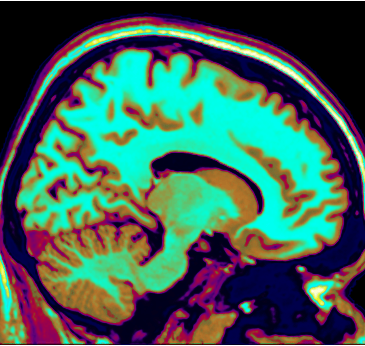

Welcome to the Deafness and Neural Plasticity Lab, run by Dr. Velia Cardin. We are interested in understanding how the human brain works, and what are the possibilities to enhance and change its function.

Our primary line of research is on human deafness. We want to understand how the brain reorganises in people who are deaf and hard of hearing, and how this impacts cognition and perception.